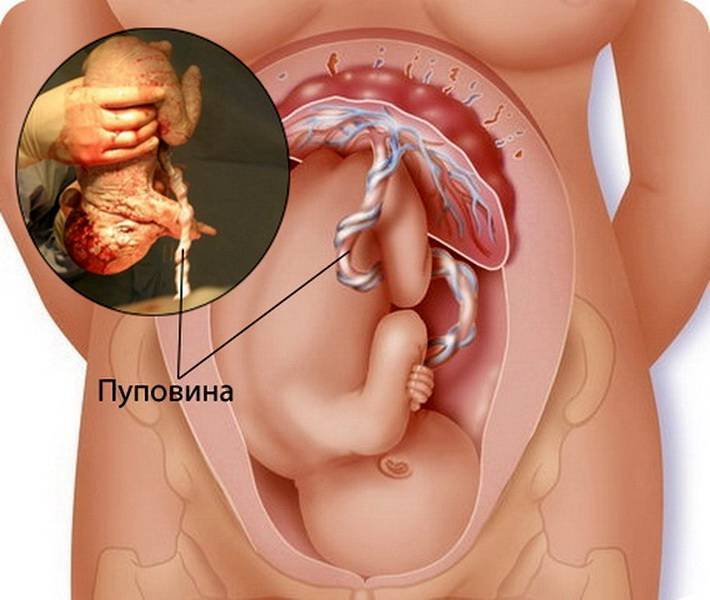

Многоводие при беременности: симптомы и лечение